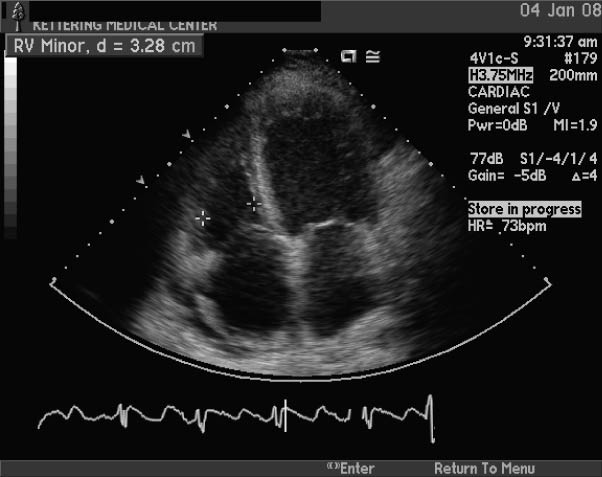

HYPERTROPHIC CARDIOMYOPATHY - Heart

HYPERTROPHIC CARDIOMYOPATHY Most often diagnosed during infancy or adolescence, hypertrophic cardiomyopathy (HCM) is the second most common form of heart muscle disease, congestive heart failure or other more obvious symptoms of HCM. ... Fetch Full Source